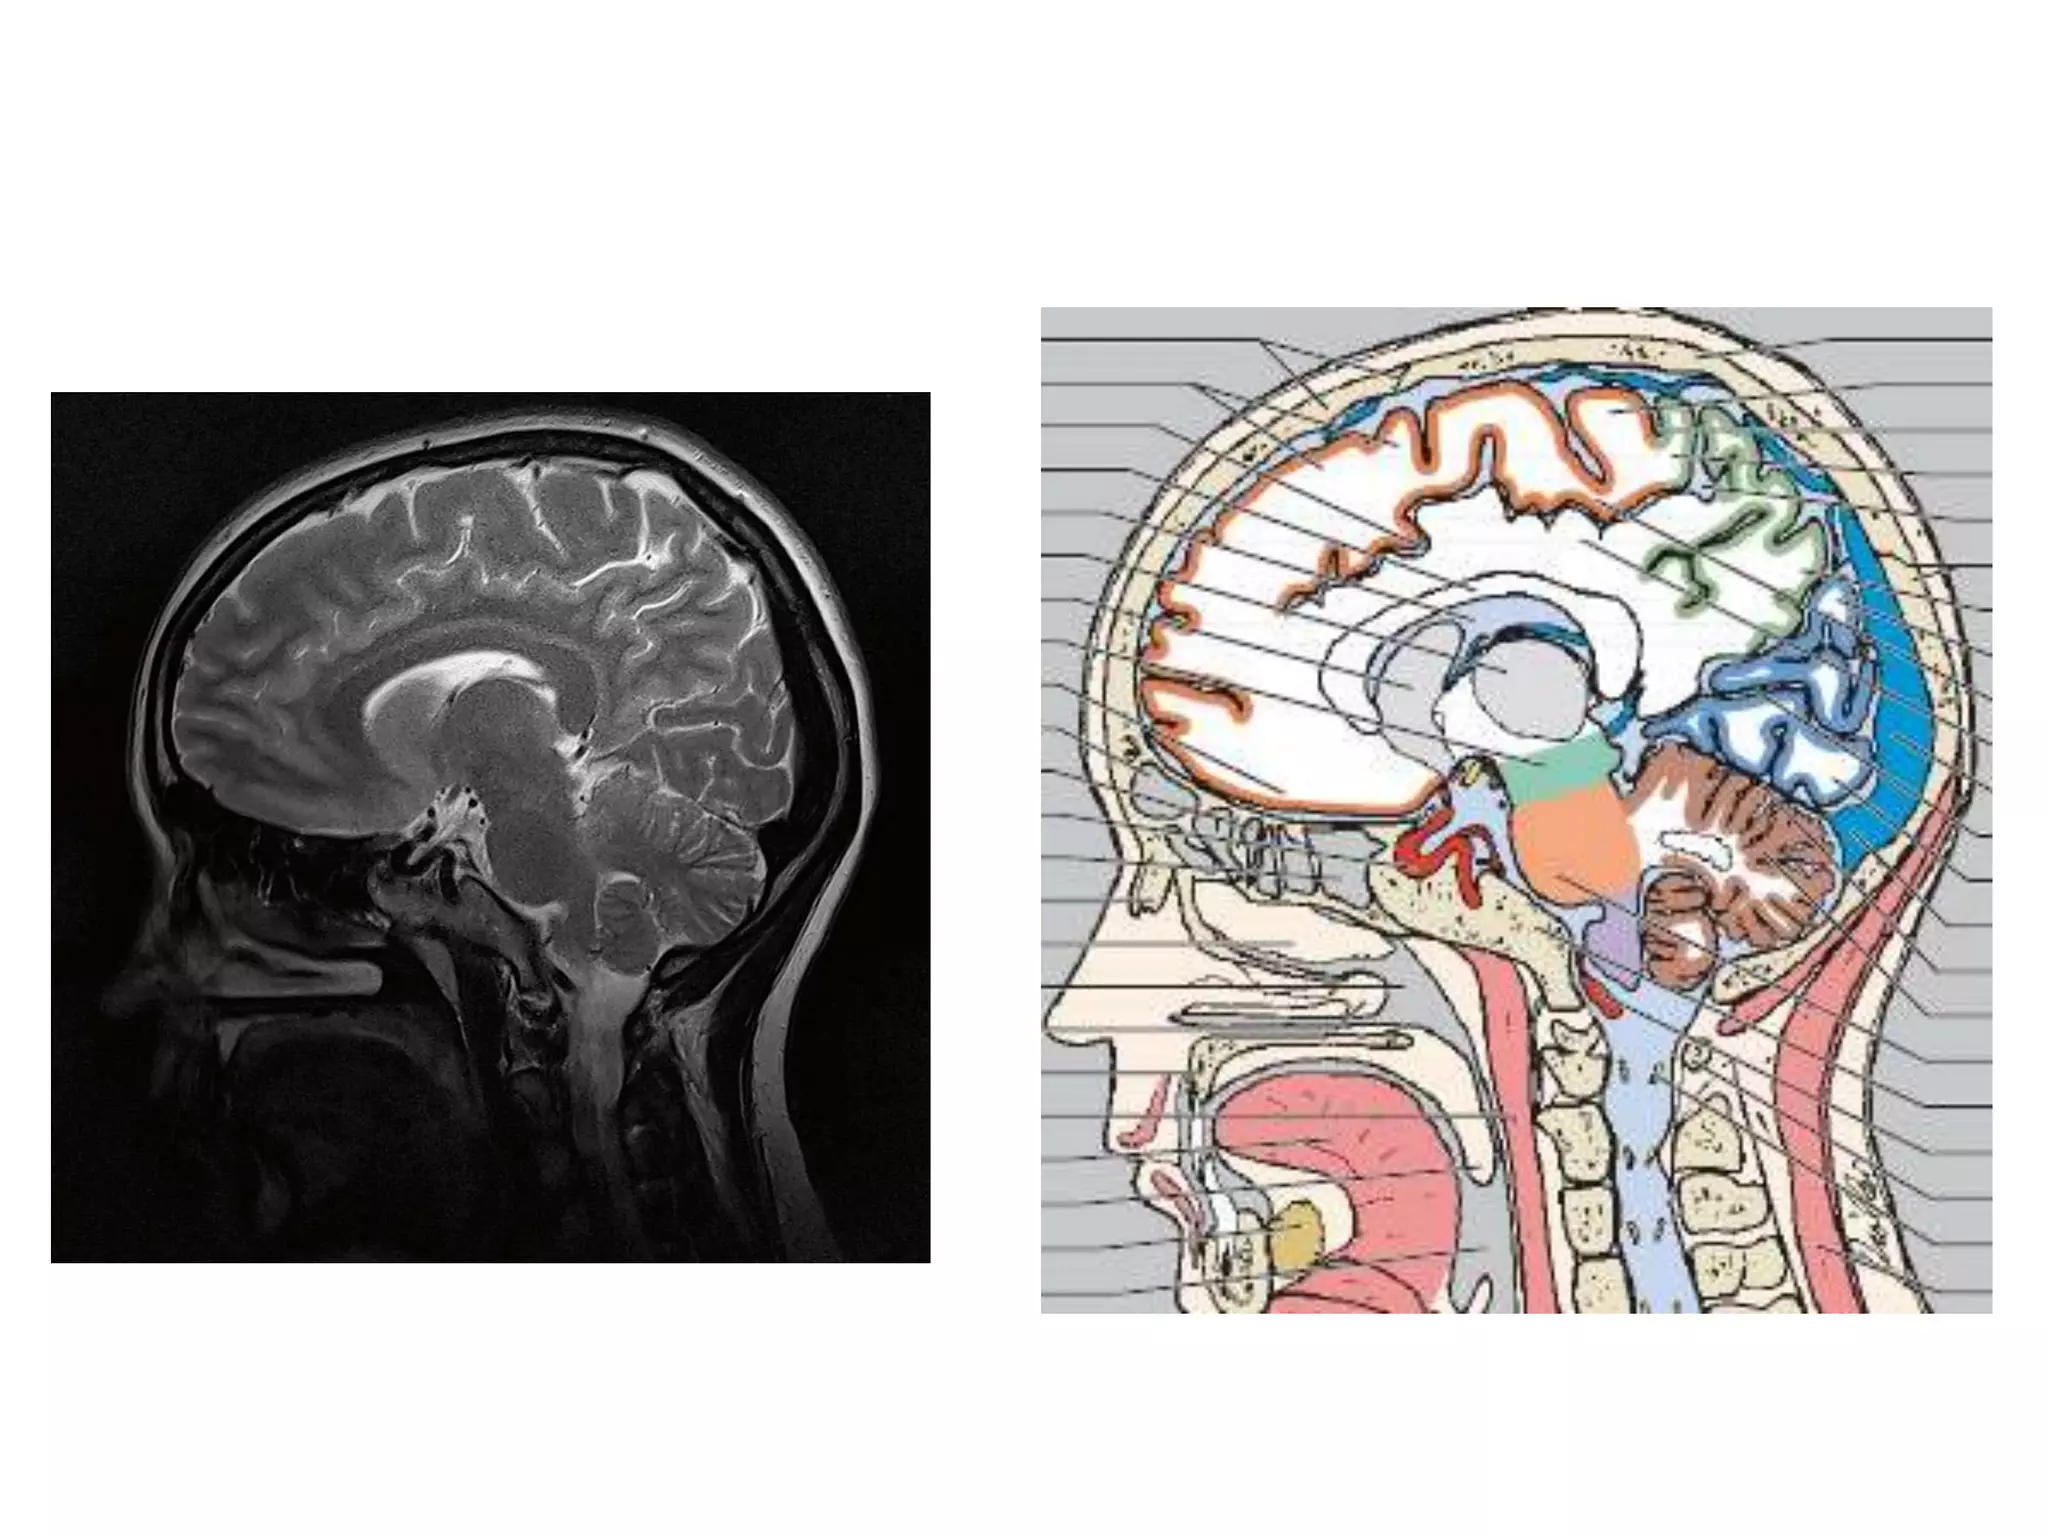

• Saggital and Coronal T1 weighted MRI – accurate

assessment of ventricles and C. callosum

• Mid Saggital section – for shape and configuration

of Aqueduct of Sylvius.

Saggital MRI : ‘C’ shaped , curving round the

thalamus.

Saggital MRI – elongated and complex curved shape

with upward, backward & downward arc.

Aqueduct of sylvius

• Relations – antr. , Postr.

• Communications

• Radiology –

Saggital MRI: concavity that curves downward

and forward towards the floor of 3rd ventricle.